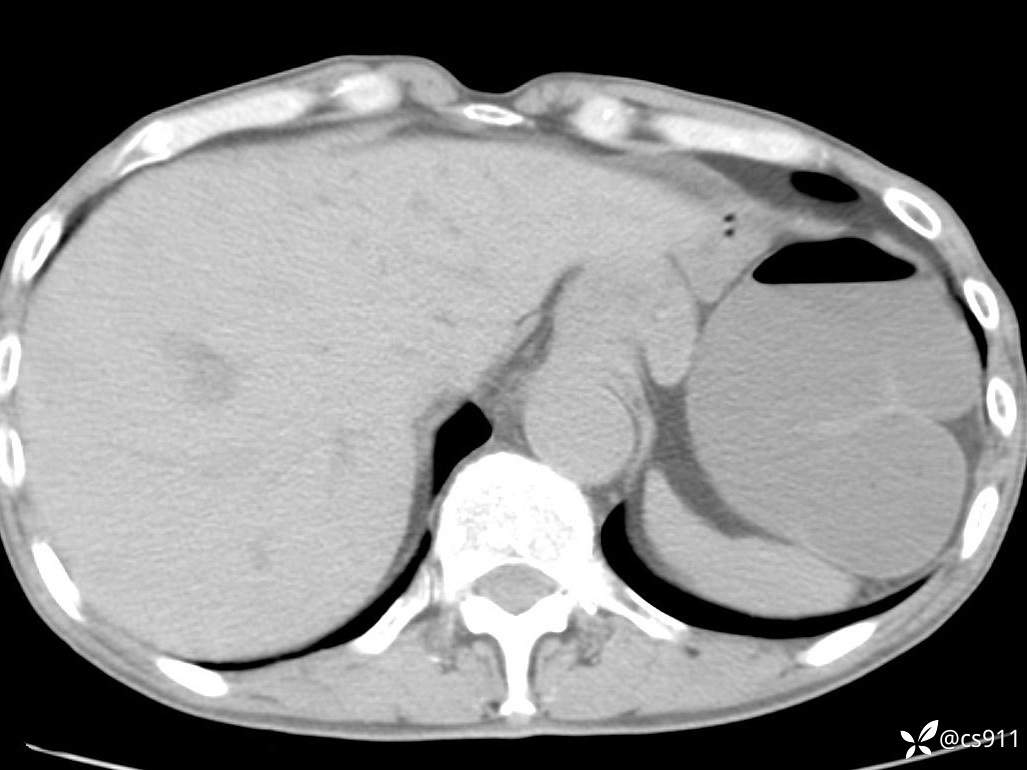

急腹症之急诊CT,原因?答案公布

男,77岁,腹痛、腹胀伴恶心呕吐1天。呕吐胃内容物,非喷射性呕吐,有咖啡色样胃内容物,诉有胃穿孔病史。查体:全腹平,下腹部压痛,全腹无反跳痛,叩诊呈浊音,移动性浊音阴性,肠鸣音减弱,1-2次/分。肛检:直肠未扪及明显肿物,可触及大量粪块。

血淀粉酶(AMY) HH 1859 U/L 35-135